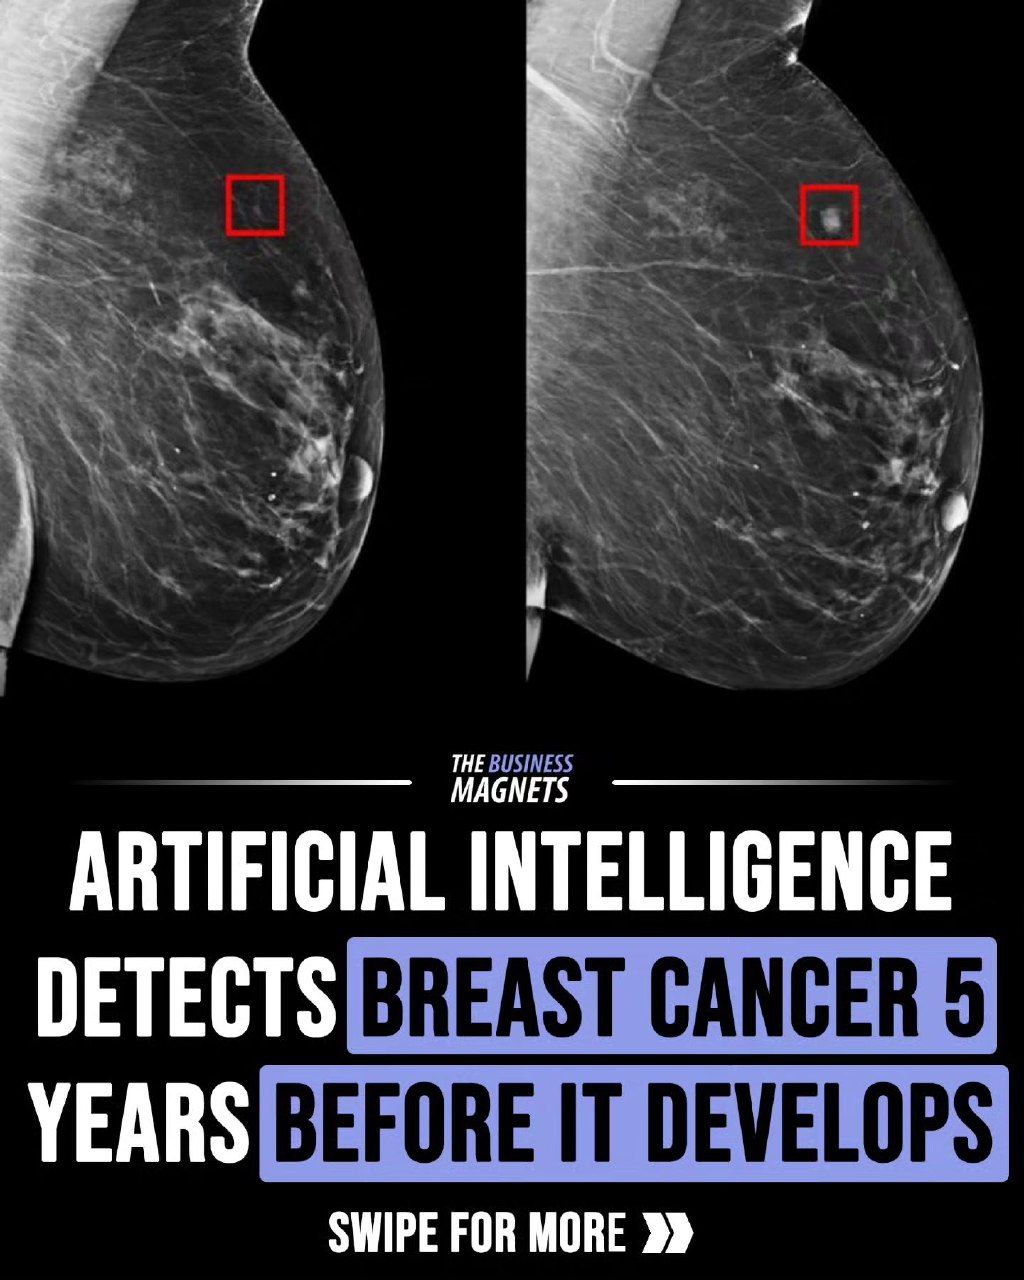

Data That Shows Early Detection Rather Than Late Detection In Breast Cancer